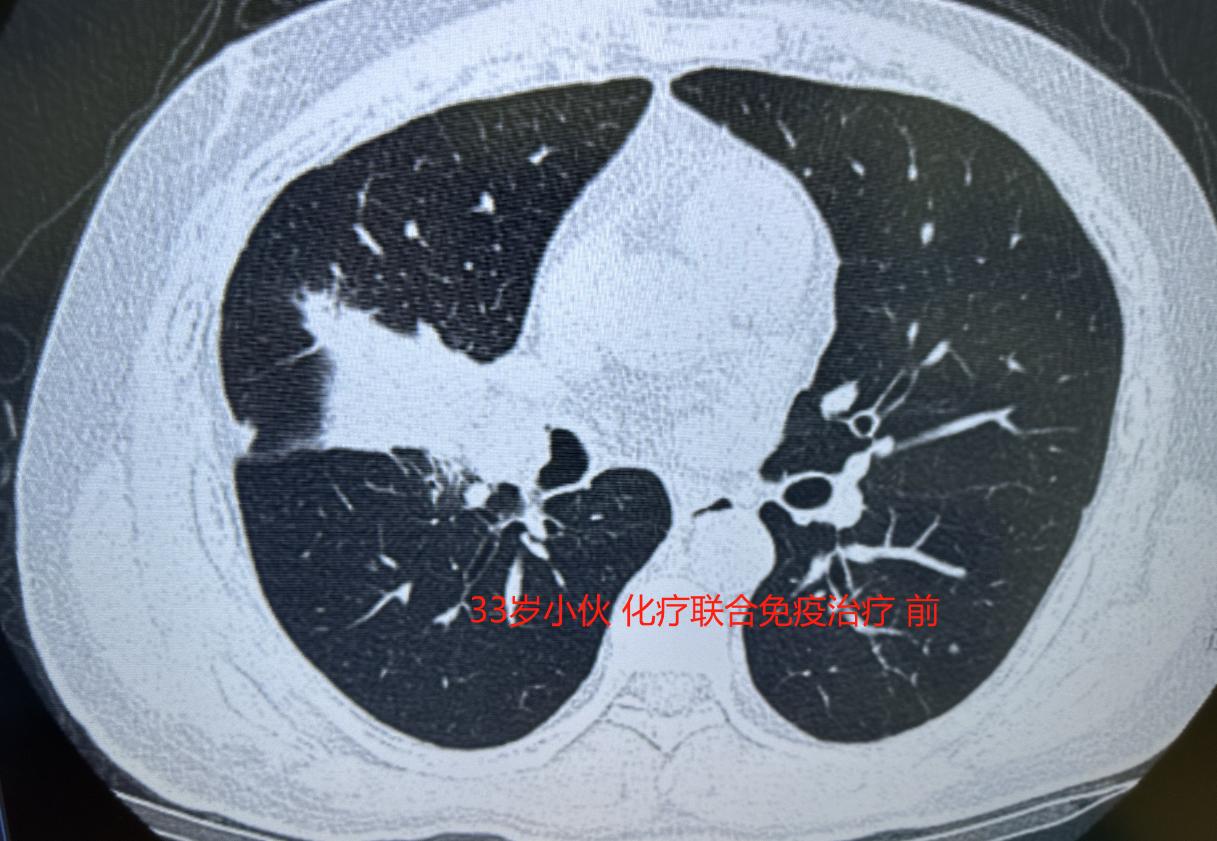

骇人听闻!在一次演讲中,北京中医药大学的曲黎敏教授提出了一个令人震惊的观点:“有钱人死得比穷人更快,因为他们花大价钱治病,结果可能适得其反。” 在一场坐得满满当当的线下讲座上,北京中医药大学的曲黎敏教授拿着话筒一开口,就把全场人都震住了。“一旦得了癌症,越有钱的人死得越快。” 这句话刚落地,原本还带着点嘈杂的教室瞬间安静下来,前排的学生停下了记笔记的手,后排架着手机录像的中年人也愣了神,满场都是倒吸冷气的“啊?”声,谁也没料到会听到这样颠覆性的说法。 台下的议论声刚要冒头,曲黎敏教授接着补充了完整的观点,这也是她原话的核心:“有钱人死得快,是因为他们以为自己有钱,就能全力以赴用新药、找最好的医生,结果反而适得其反。 那些所谓的好药、新药,很多都是刚研发出来的,我们对它们的副作用了解得还不全面,有钱人不知不觉就成了新药的实验对象,最后付出了巨大代价。” 这番话让原本哗然的现场再次陷入寂静,大家都跟着她的思路开始琢磨,这话听着刺耳,可好像真有几分道理。 她提起的贝壳创始人左晖的例子。2021年夏天,左晖因肺癌去世的消息传开时,很多人都不敢相信,毕竟这位身家百亿的企业家前阵子还在财报会上露面,声音硬朗得很。 可熟悉内情的人都知道,他2018年就查出了问题,一开始只是咳嗽,以为是熬夜、雾霾导致的小毛病,拖到确诊时已经不是早期了。 有钱的优势在这时变成了“负担”,家人请了国内顶尖的肿瘤科、呼吸科专家会诊,一套套治疗方案轮番上,几万一盒的靶向药医保都不报销,吃了没几个月指标刚有点回落就又反弹。 家属急得不行,又听朋友说国外有新技术、新药,于是开始了无休止的折腾。北京、上海、广州来回跑,VIP病房按年包,护工轮班值守,晚上十二点病房的灯还亮着,家属对着iPad查美国的临床数据、翻译外文文献,就盼着找到救命的办法。 后来甚至飞赴北美顶级癌症中心,找人插队挂专家号,一个疗程下来副作用猛得很,左晖瘦得走路都打晃,却还得硬撑着开视频会议。有人说,他单次治疗的费用就能在北京三环买套小两居,可钱花得像流水,人却走得比很多普通病人还快。 曲黎敏教授说,这不是个例,她见过太多这样的有钱人。他们生病后总觉得“钱能解决一切”,医生们各持己见推荐不同疗法,家属没了主意,就认准“最贵的就是最好的”。 而药厂也看准了这个心理,新药一出来就大肆宣传疗效,朋友圈里全是相关截图,把有钱人当成了推广新药的“试验田”。 反观那些普通家庭的病人,没多少钱折腾,只能老老实实在本地医院跟着治疗指南来,心态反而更平稳,不瞎折腾,身体反倒能稳住阵脚。 当时台下有个穿西装的中年人不服气,举手问:“老师,难道有钱还成错了?”曲黎敏摊了摊手,说她不是否定有钱的好处,而是想提醒大家,健康这事儿真不是靠钱堆出来的。 很多时候,有钱人的病不是被癌症本身拖垮的,是被自己的恐慌心态和无休止的折腾耗光了最后一点底子。 就像她遇到的一位老干部,不抽烟不喝酒,却查出了肺癌,究其原因就是活得太压抑,情绪长期憋在心里没处宣泄。后来老干部听了劝,辞了职天天陪老伴逛公园、跳广场舞,心态放松了,反而多活了好几年。 其实曲黎敏教授想表达的核心很简单:治病讲究的是顺势而为,不是盲目跟风。那些被大家追捧的新药、新技术,未必适合每个人,过度治疗反而会伤了身体。 就像她常说的“凡是浓烈的,都可能致命;凡是平淡的,都是养生之道”,健康从来不是靠钱买的,平稳的心态、规律的作息,比任何天价药都管用。 这话听着颠覆,却戳中了很多人的误区,也难怪当时全场听完都恍然大悟,原来真正的养生,拼的从来不是财力,而是通透的心态。